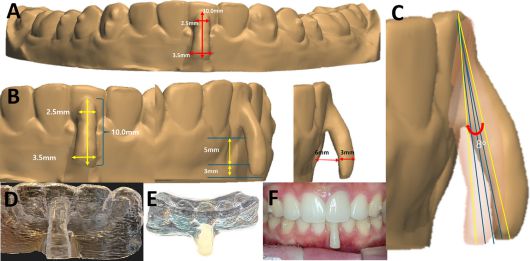

이번 논문은 국내 최초로 투명교정만으로 퇴축된 잇몸을 재생시킨 임상 보고로, 하악 전치부에서 5mm의 잇몸퇴축이 11개월간의 교정치료 후 1mm로 회복되는 임상 결과를 확인했다. 치조골과 잇몸조직이 자연스럽게 복원되는 과정을 객관적 데이터로 제시했다는 점에서 의미가 크다.

‘오버행잉 어태치먼트’는 치근 이동 시 발생하는 토크(torque)를 정밀 제어해, 치아의 중심저항점(center of resistance)에 가까운 위치에서 힘을 전달하도록 설계됐다. 이를 통해 정확한 치체이동(root movement)이 가능해지고, 결과적으로 잇몸재생이 유도된다.